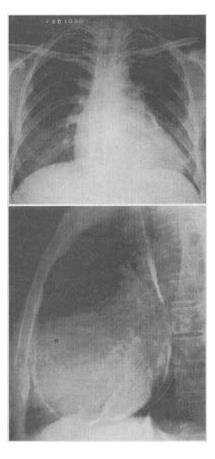

患者,男,34岁,心悸、腹胀,胸片如图,最可能的诊断是()。

A、心包积液

B、缩窄性心包炎

C、扩张性心肌病

D、肥厚性心肌病

E、风湿性心脏病二尖瓣狭窄

B